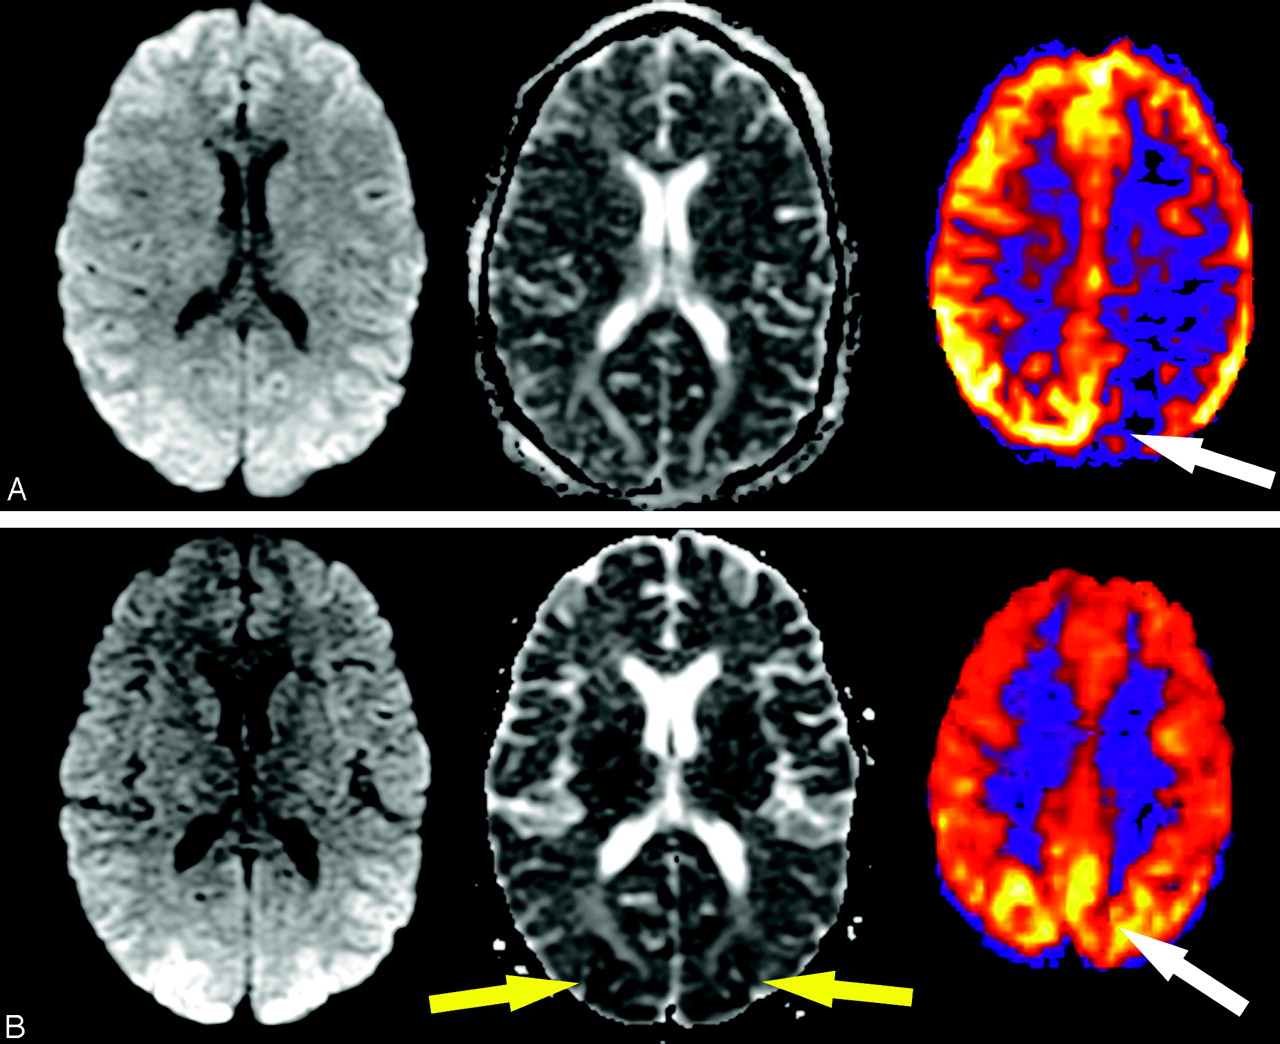

PRES and PRES-like syndromes can occur spontaneously or in association with uncontrolled hypertension, eclampsia, and cyclosporine toxicity and as a complication of certain chemotherapeutic regimens.14–16 A loss of autoregulatory control occurs in these syndromes, and initial attempts to maintain perfusion pressure result in arteriolar vasoconstriction. Hyperperfusion follows and results in reversible edema, more commonly in the vertebrobasilar vascular territories likely because of the relatively fewer perivascular sympathetic nerves in this area.14 Figure 11 demonstrates changes with time in a 31-year-old patient with PRES, including initial vasoconstriction and hypoperfusion followed by rebound hyperperfusion. ASL is a robust technique in the evaluation of hyperperfusion syndromes due to its repeatability and its strength in depicting high-flow states. Figure 12 demonstrates a case of post-endarterectomy hyperperfusion syndrome in a patient who had recently undergone ipsilateral carotid endarterectomy. This is a well-described phenomenon using other perfusion techniques17 and is presumed to result from loss of autoregulatory function.

Evolution of perfusion changes in PRES in a 31-year-old woman. A, Initial images: high signal intensity on the initial diffusion-weighted image (left) represents T2 shinethrough secondary to edema seen on the apparent diffusion coefficient (ADC) images (center) in the occipital cortices. A corresponding ASL map (right) reveals marked flow asymmetry with hypoperfusion in the left occipital lobe (white arrow). B, At 2-week follow-up, diffusion and ADC images show new posterior restricted diffusion (yellow arrows), and bilateral hyperperfusion is now evident on perfusion images (right, white arrow).